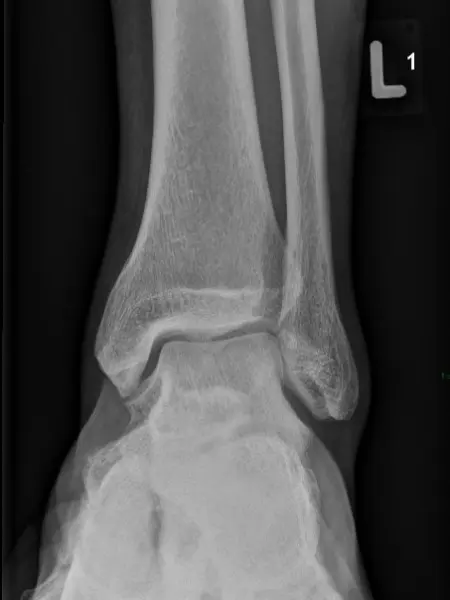

Zdjęcie RTG prawidłowego stawu skokowego – widok od przodu Zdjęcie RTG prawidłowego stawu skokowego – widok od przodu

Zdjęcie RTG prawidłowego stawu skokowego – widok z boku Zdjęcie RTG prawidłowego stawu skokowego – widok z boku